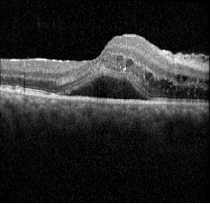

Ocular coherence tomography (OCT) images for both eyes revealed subretinal and intraretinal fluid, as well as hyperreflective material within the retina.